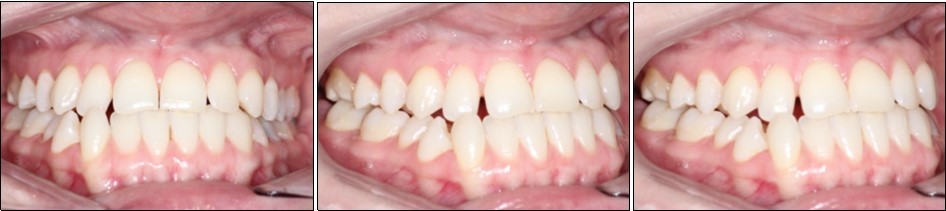

Intraoral examination revealed bilateral Angle’s class III molar relationship, class III canine relationship on the right and class I on the left, a deviated lower dental midline to the left of the patient, a visible negative tip in the right upper lateral incisor and canine, crossbite between 1.2. and 4.3 and 4.4, retroclined lower incisors, proclined upper incisors, with a 1 mm overbite and overjet . (Figure 2)

Figure 2.Initial intraoral photographs